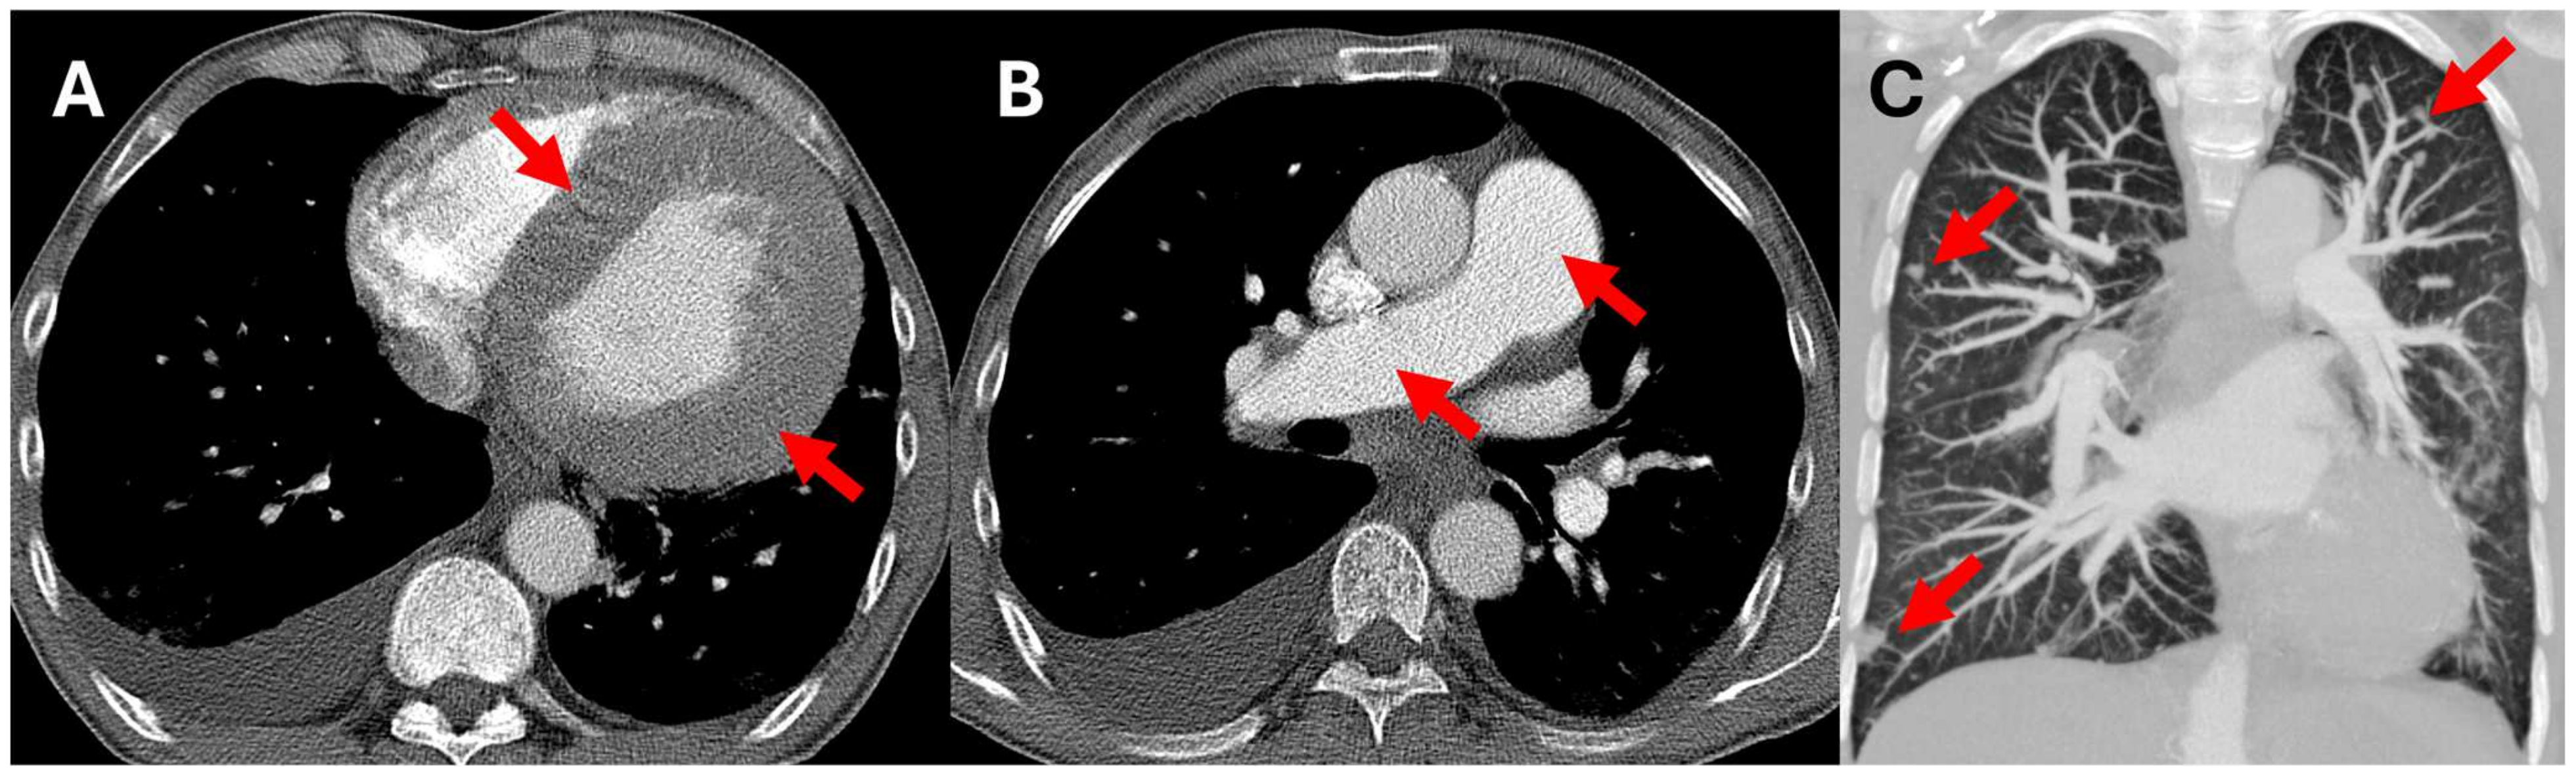

2. Case Presentation